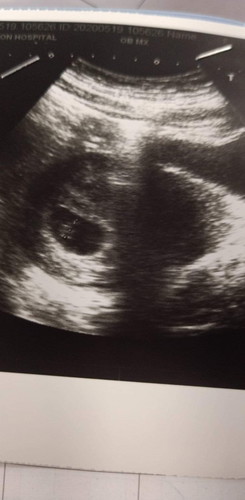

พอดีไปหาหมอ แล้วหมอซาวด์เห็นแบบนี้แต่หมอไม่แน่ใจว่ากี่สัปดาห์แบ้วมีใครพอเดาๆได้บ้างมั้ยคะ เพราะหมอบอกว่าน่าจะยังไม่ถึง6สัปดาห์ แต่ไม่รู้ว่ากี่สัปดาห์แล้ว